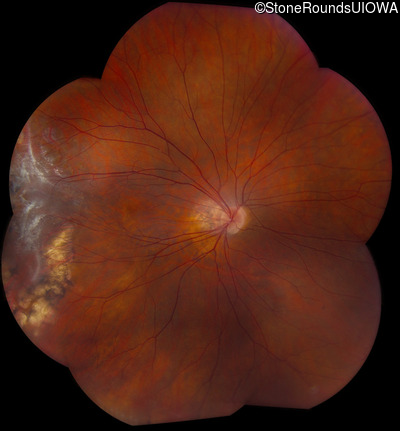

AD Familial Exudative Vitreoretinopathy (IIIE2b)

Age at visit: 32 years

This 32 year old woman has had subnormal acuity (right eye worse than left eye) since very early childhood.